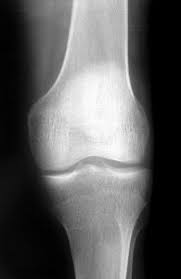

Fy och bläää, jag tycker så synd om Bernhard... bakre korsbandet av och 6 månaders rehabträning!

Tycker synd om hela familjen eftersom jag vet hur påverkad man blir när en skada händer, inte bara kroppsligt utan även psykiskt.

Det var E och Bernhard som krockade på en träning, när E kom hem så var han otroligt nere och mådde dåligt, för att det oturligt nog blev en knä mot knä krock och Daniel hade fått riktigt ont och avbröt träningen.

E och Bernhard umgås väldigt mycket och självklart så svider detta oerhört.

Men jag vet att Bernhard är av segt bonde virke och han ger inte upp i första taget!!!

Själv så var jag ner till läkaren i Gävle i fredags, och han tror att det är menisk skada och korsbandet av.

Läkaren remitterade mig till Magnetröntgen i Uppsala, så på måndag får jag min MR tid och enligt läkaren så skulle det gå väldigt fort, och det känns så himla bra!!